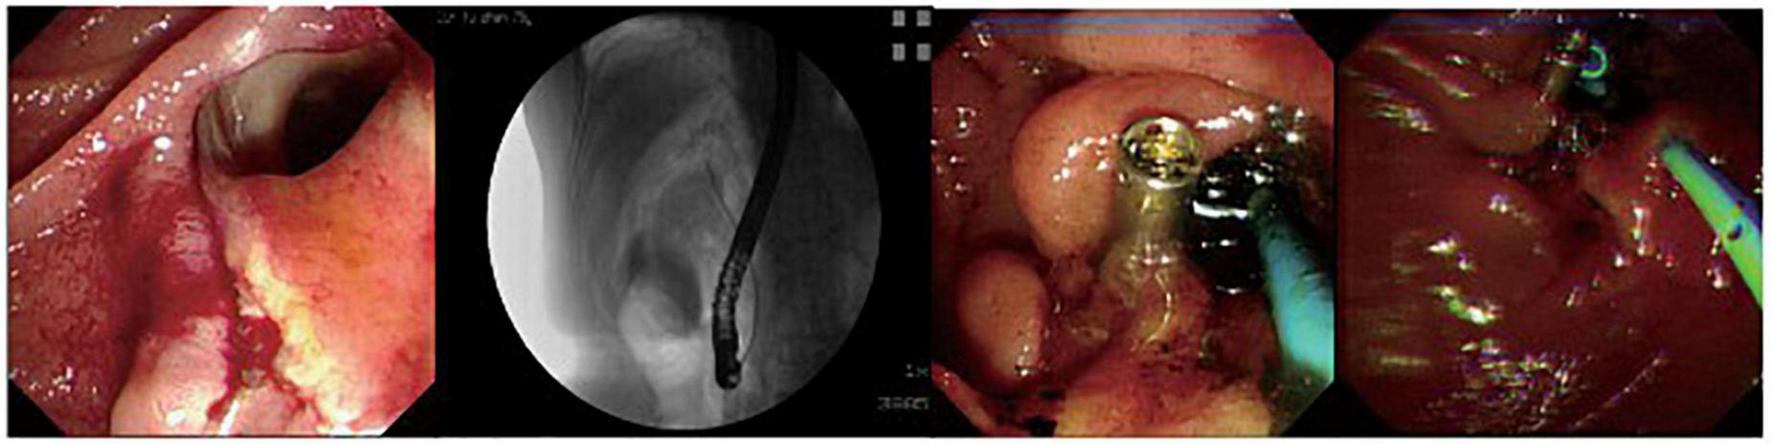

FIGURE 2

A patient with peri-ampullary perforation received ERBD and ERPD. The perforation had signs of retroperitoneal and peritoneal perforation.

The fundus perforation, the peri-ampullary diverticulum perforation, and eight duodenal perforations were treated by closing the lesion, performing endoscopic nasobiliary drainage (ENBD) or endoscopic retrograde biliary drainage (ERBD), conducting gastrointestinal decompression, and using proton pump inhibitor (PPI), somatostatin (SS), and broad-spectrum antibiotics for 5–7 days. Each lesion was closed by clips, purse string sutures, or over-the-scope-clip (OTSC) (Figures 1–3). Three afferent limb perforations and three duodenal wall perforations were treated through surgery. The small bile duct perforation on the liver surface, the residual duct of gallbladder perforation, and the 26 peri-ampullary perforations were healed through nasobiliary drainage or biliary stenting drainage, gastrointestinal decompression, and using PPI, SS, and broad-spectrum antibiotics for 5–7 days. Biliary stents are typically 8.5 Fr × 7 cm in size, whereas pancreatic stents are typically 5 Fr × 5 cm in size. If no unusual conditions exist, the stents will be removed after 1 month of satisfactory drainage. Three patients received endoscopic retrograde pancreatic drainage (ERPD) at the same time. The 81-year-old female patient with a duodenal wall perforation, which had been closed with OTSC, died of heart failure and post-ERCP pancreatitis 3 days after the ERCP procedure. The other patients recovered successfully (Figure 4). Management outcomes of the 45 patients were summarized in Table 3. The mortality was 2.2% (1/45).